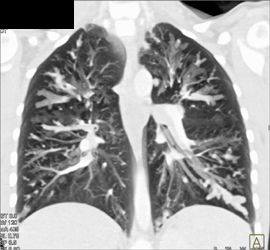

Cystic Fibrosis